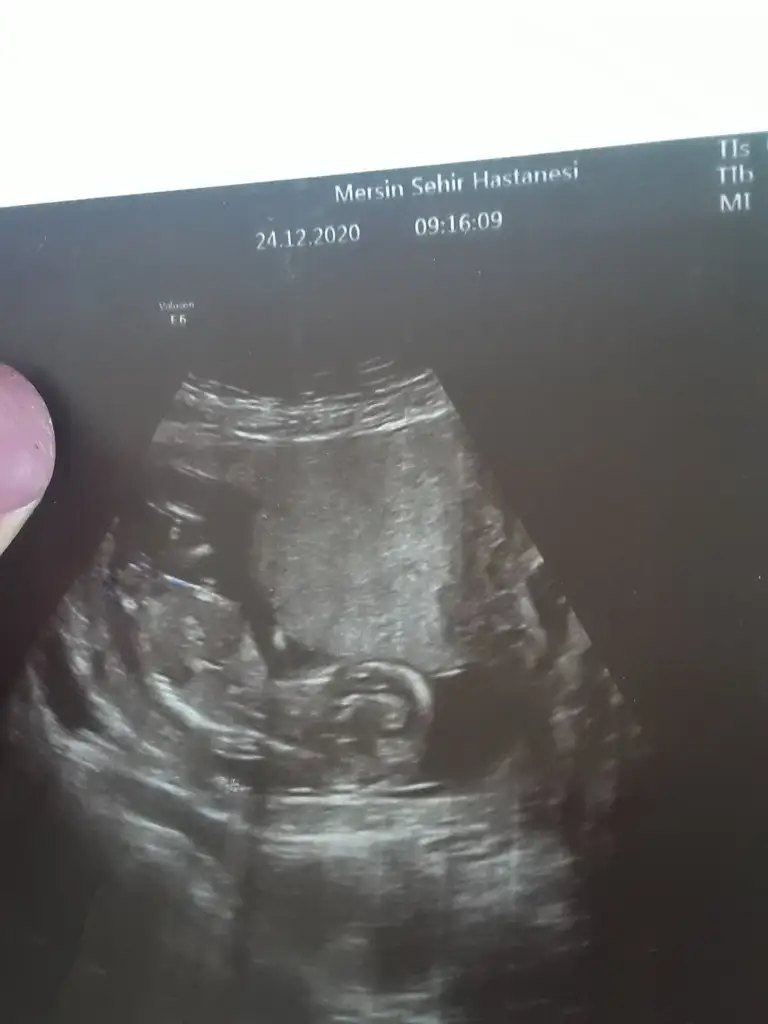

Erkek görünüyorMerhaba kızlar, 12+3 haftalığız bugünki ultrason görüntümüz. Doktorumuz bir tahmin yaptı bakalım sizce nedir cinsiyeti?

Çok net değil USG kız diyecem ama emin değilimBiz de bugün 12+0 çıktık ultrasonda doktor yüzde 60lık bir tahmin yaptı ama size de sormak istedim :)Ikra meyra

Erkek görünüyorIkra meyra merhaba Banada bakarmısınız lütfen 2 hafta önce de yazmıştım doktor a gittim bugün

Bebek baş aşağı yorum nasıl yapacam şaşırdım